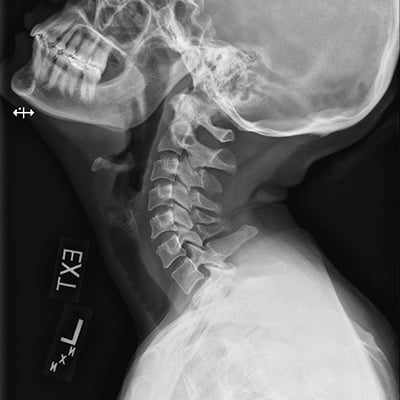

This module will help you achieve optimal images when performing cervical, thoracic, and lumbar spine examinations. Patient preparation and positioning are discussed, as well as technical settings and patient instructions. Descriptions and images of the expected anatomical structures are included, as well as image evaluation criteria.